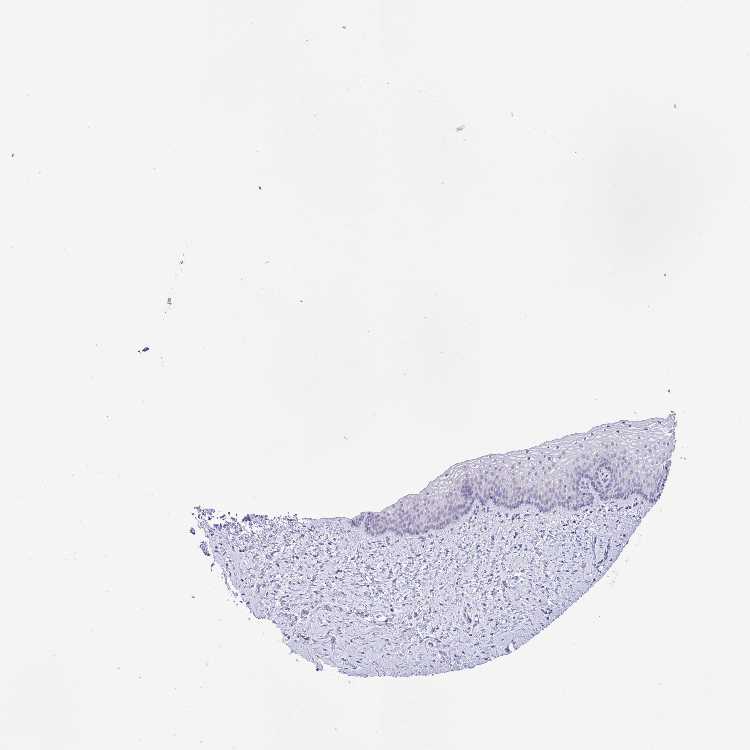

VAGINA - Antibody stainingi

Antibody staining in the annotated cell types in the current human tissue is reported as not detected, low, medium, or high, based on conventional immunohistochemistry profiling in selected tissues. This score is based on the combination of the staining intensity and fraction of stained cells.

Each image is clickable and will lead to virtual microscopy that enables deeper exploration of all samples and also displays staining intensity scores, fraction scores and subcellular localization as well as patient and tissue information for each sample.

Antibody HPA046811Antibody HPA058495

Squamous epithelial cells Not detectedLow